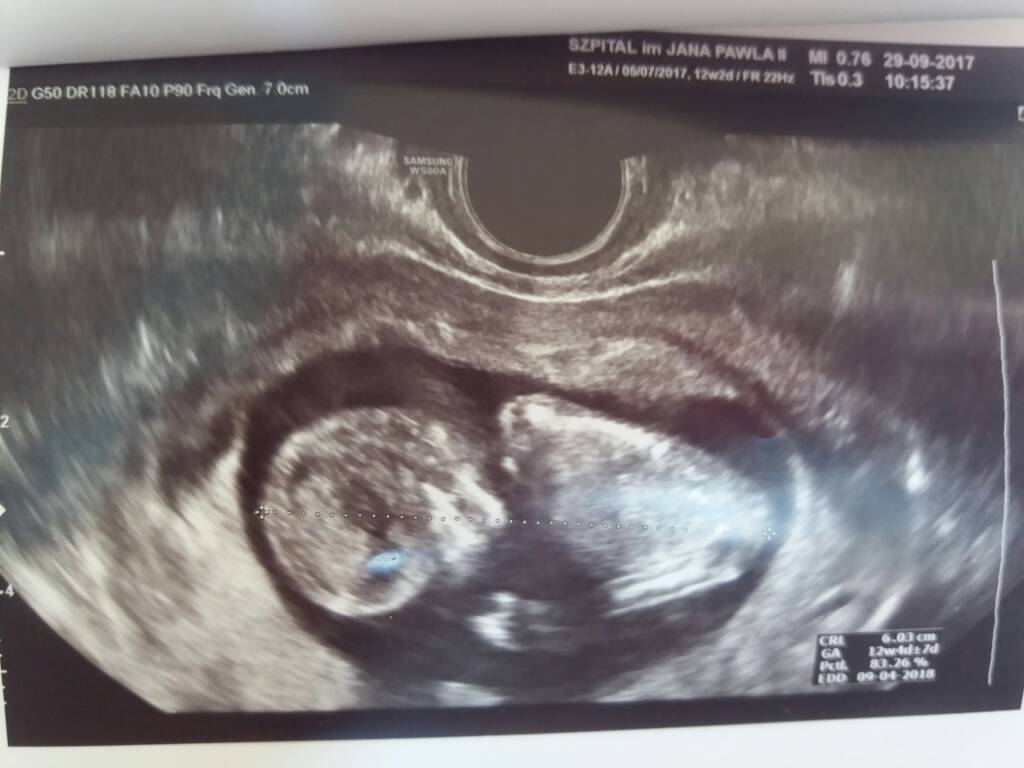

Witam dziewczyny,

Dawno tu nie zaglądałam. Z m wyjechaliśmy na kilka dni nad morze odpocząć i bylo super...

Dziś byliśmy na kolejnym usg, bardzo byłam zestresowana i praktycznie w nocy nie spałam.

Na szczescie wszystko jest ok, bobas bardzo aktywny i ciezko bylo mu/jej zdjęcie z profilu zrobic :)

Ust miało również sprawdzić prawdopodobieństwo wystąpienia zespołu Downa, wraz z krwią ostateczne wyniki maja przyjść do 2 tyg i znów czekanie...

Dołączam zdjatko bobaska :)